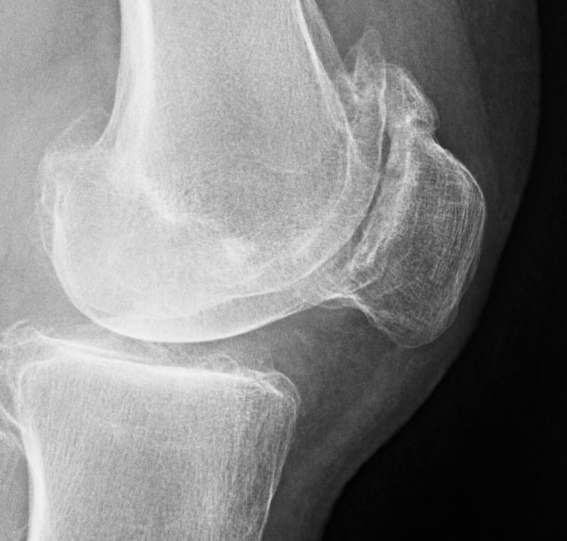

X-ray

Narrowing / osteophytes / sclerosis

Tilt / subluxation

Tilt Subluxation / osteophytes

Moderate lateral facet PJF OA with tilt

Severe lateral PFJ OA in the setting of maltracking / subluxation / tilt